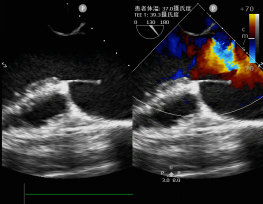

随后,李某转院至四川大学华西医院,进一步完善检查发现,超声心动图提示她的主动脉根部动脉瘤直径达6.5cm,破裂或发生主动脉夹层的风险较大,随时可能危及孕妇和胎儿生命。与此同时,患者李某的主动脉瓣重度反流、心脏功能下降,左心射血分数仅为43%,胸部血管CT还提示主动脉根部和升主动脉明显扩张等等。

患者李某全麻后,肖正华副教授和宋海波教授通过食道超声仔细评估瓣膜情况,发现患者虽然主动脉瓣重度反流,但瓣膜的质量不错,具备修复的基本条件。但是,团队术中又发现患者动脉瘤巨大,局部组织已经变薄,颜色变为苍白色,提示血管质量不佳,随时可能破裂,无疑给手术也增加了难度。

复杂的手术流程后,团队再次经食道超声确认和衡量手术效果,确定手术成功。

术后第六天,复查超声心动图结果提示患者心功能已基本恢复正常,主动脉瓣微量反流,手术效果显著。